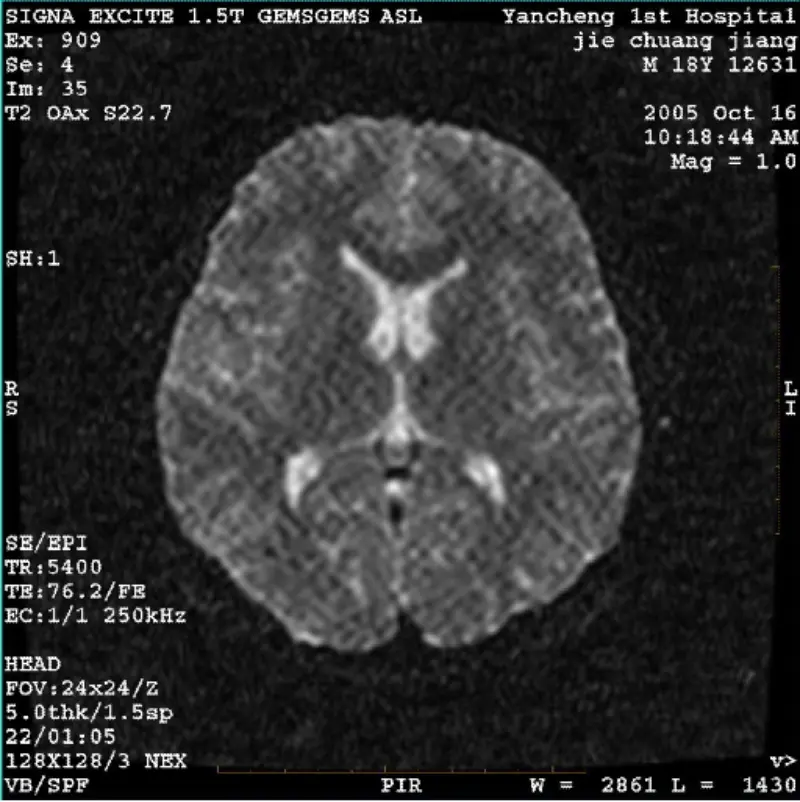

ఇంకా చదవండిసిస్టమ్: 1.5T సిగ్నా ట్విన్ ఎక్సైట్ II (సాఫ్ట్వేర్ వెర్షన్ 11.0M4) సమస్య/లక్షణం DWI (జూమ్ మోడ్ మరియు మొత్తం మోడ్) మరియు ఫియస్టా (జూమ్ మోడ్ మరియు మొత్తం మోడ్) ఇమేజ్ కలిగి ఉంది బాడీ కాయిల్ లేదా హెడ్ని ఉపయోగించినప్పుడు కనిపించే రెటిక్యులేట్ లేదా కార్డ్రోయ్ కళాఖండం కాయిల్, ఇతర సాధారణ చిత్రం సా......